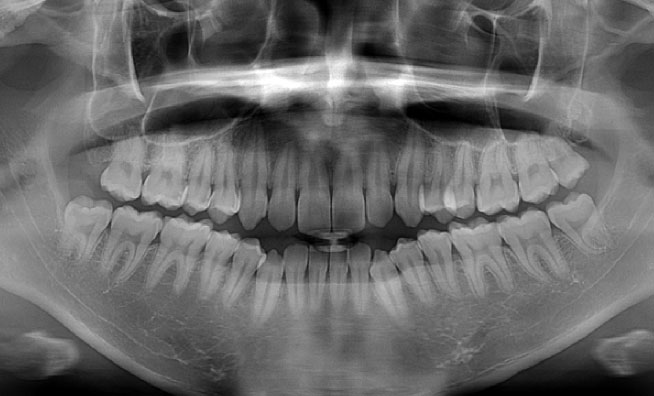

尼崎市ほほえみ歯科では、インプラント治療をはじめ、根管治療や親知らずの抜歯、矯正治療など、正確な診断が求められる治療においてCT撮影を積極的に取り入れています。

通常のレントゲンとは異なり立体撮影が可能になるため、顎の骨の形や歯根、神経の位置といったデータも取得できます。歯や骨の状態をさまざまな角度から把握できるため、得られる情報量が多く、より精度の高い診断につなげることができます。